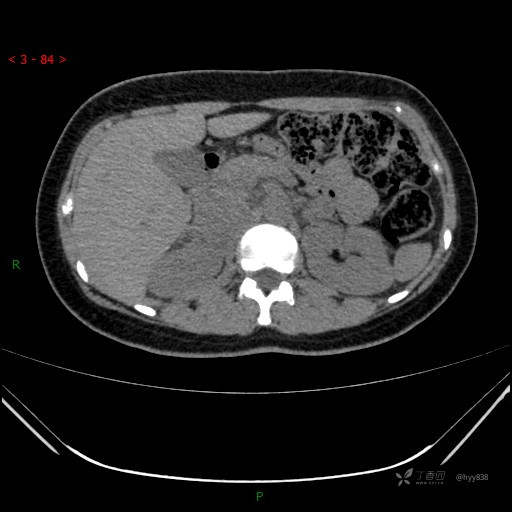

肾上腺CT平扫